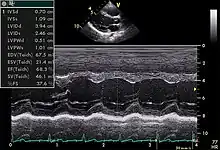

| Echocardiography | |

An abnormal echocardiogram: Image shows a midmuscular ventricular septal defect. The trace in the lower left shows the cardiac cycle and the red mark the time in the cardiac cycle when the image was captured. Colors are used to represent the velocity and direction of blood flow. | |

Echocardiography, also known as cardiac ultrasound, is the use of ultrasound to examine the heart. It is a type of medical imaging, using standard ultrasound or Doppler ultrasound.[1] The visual image formed using this technique is called an echocardiogram, a cardiac echo, or simply an echo.

TTE utilizes one- ("M mode"), two-, and three-dimensional ultrasound (time is implicit and not included) from the different windows. These can be combined with pulse wave or continuous wave Doppler to visualize the velocity of blood flow and structure movements. Images can be enhanced with "contrast" that are typically some sort of micro bubble suspension that reflect the ultrasound waves.

Motion mode is infrequently used in modern echocardiography. It has specific uses and has the benefit of very high temporal fidelity (e.g., measuring LV size at end diastole).